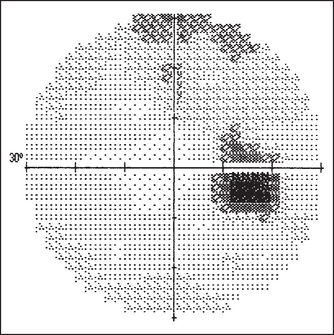

Figure 36.9 Visual field charts Both eyes superimposed. The blind spot is indicated in a darker colour. Stamper RL, Visual field interpretation. Becker-Shaffer’s Diagnosis and Therapy of the Glaucomas. 2009: Elsevier.